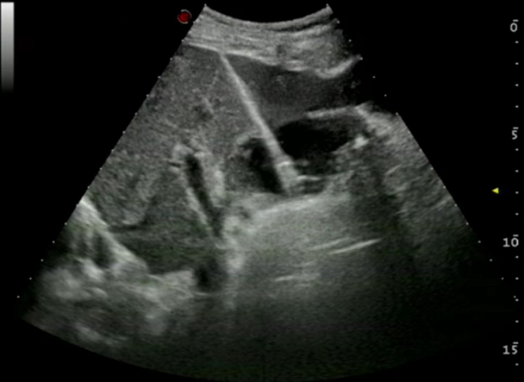

超声引导下经皮经肝胆囊穿刺置管引流术 超声引导下颈部肿物穿刺活检术 超声引导下肝肿瘤微波消融术